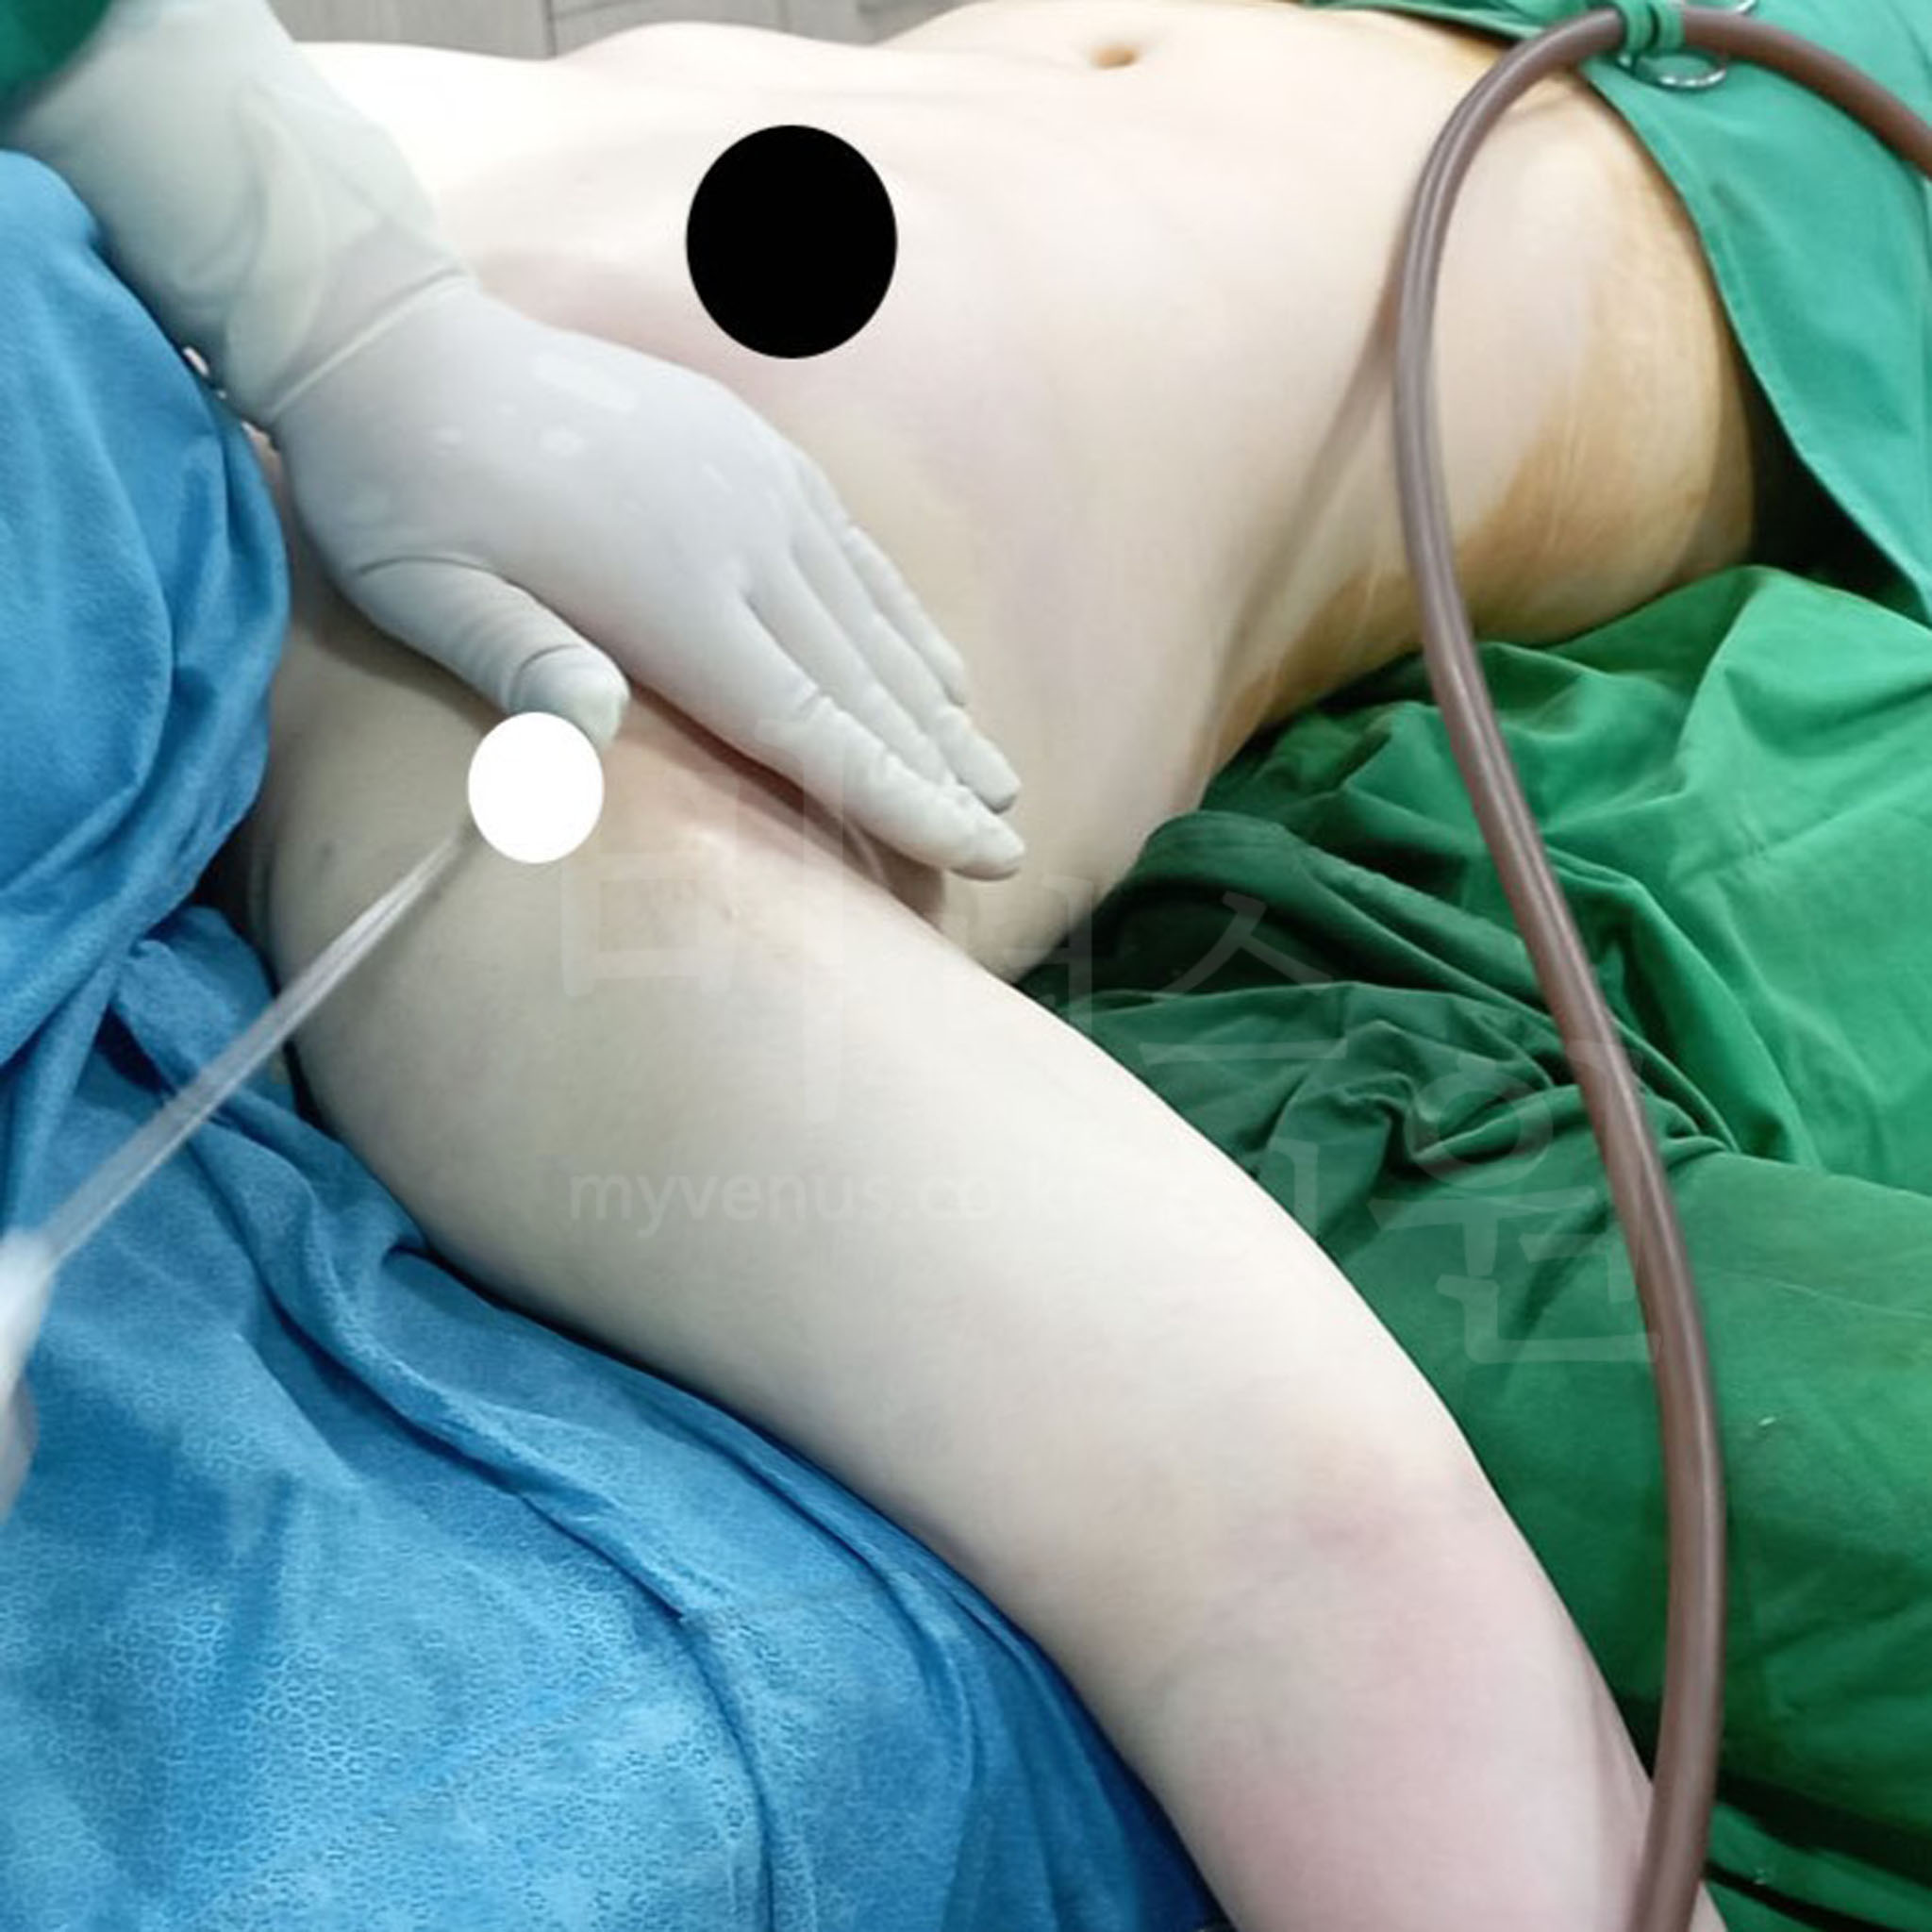

핸드메이드 리프팅으로 더 탄력 있게

섬세한 손기술로 완성하는 탄력 팔뚝

기계 대신 손으로, 정교한 리프팅 효과

비너스에서는 기계에 의존하지 않고, 시술자의 손으로 진행되는 ‘핸드 리프팅 지방흡입’을 시행합니다. 이 방법은 단순한 지방 제거를 넘어 피부에 직접 자극을 주어, 처진 피부를 절개하지 않고도 탄력 있는 결과를 얻을 수 있습니다.

흉터 걱정 없이 깔끔하게

눈에 띄지 않는 절개, 흉터 부담 없이

주름선 절개로 깔끔한 마무리

팔꿈치에 절개를 하지 않고, 겨드랑이 앞·뒤 주름선에 최소 절개를 통해 흡입이 이루어집니다. 이로 인해 흉터가 거의 눈에 띄지 않으며, 일상 속에서 보안성도 우수합니다. 지방흡입 후 흔적이 걱정되는 분들에게도 만족도가 높은 이유입니다.